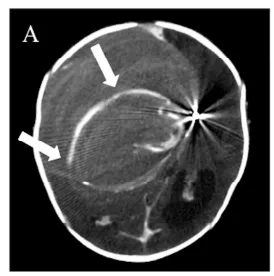

胎儿MRI进一步显示右侧大脑半球巨大血管病变,压迫邻近脑实质,导致中线结构向对侧移位,并已出现早期梗阻性脑积水(图1A-B)。

出生第1天,亨利被确认存在颅内血管病变,表现为囊状动脉瘤样结构,内部为搏动性血流。同日进行的磁共振血管成像(MRA)显示右侧额叶软脑膜动静脉瘘(PAVF),伴软脑膜静脉瘤样扩张,其内血流湍急,经扩张静脉引流入上矢状窦(图1C-E)。该病变还压迫同侧脑组织,导致局部脑实质萎缩。

因亨利临床状态稳定,医疗团队决定在其出生后第8天施行数字减影血管造影(DSA),以完成血管内栓塞治疗。术后即刻造影显示主瘘道实现完全闭塞(图2C)。

术后第1天,其神经状态出现轻度恶化。急诊CT显示瘤囊内血栓进展、囊腔较前增大;CTA发现右侧大脑中动脉(MCA)远端新发出一支粗大供血支参与瘘口(图3A),该支在术前DSA中未显影。